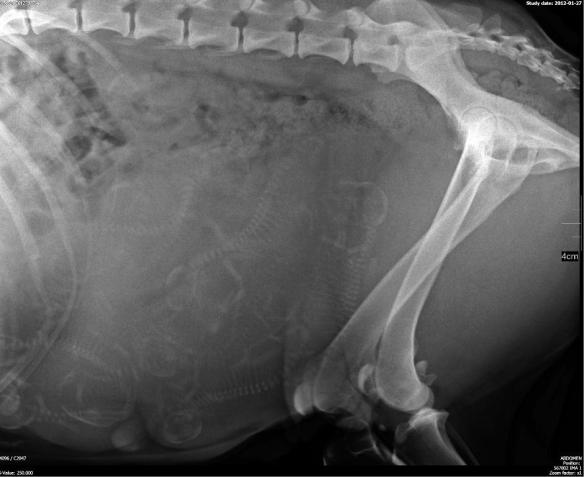

Patrzymy na dostojnie spacerującą, rzadko kawałek podbiegającą, ale głównie śpiącą Achaję. Głaszczemy wielgachny, czasami podskakujący pod ręką brzuszek. Namówieni przez weterynarza (po wielokrotnym zapewnieniu, że jest to bezpieczne) zaglądamy do środka (RTG). Kto policzy z nami?